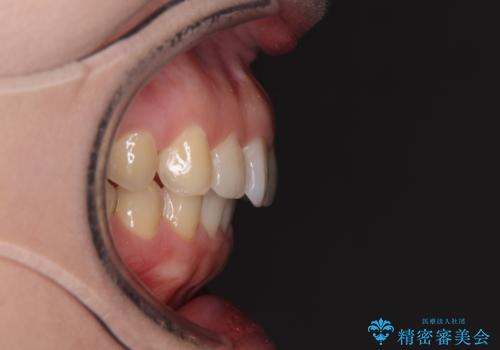

インビザライン矯正で前歯のデコボコを改善

骨格的に下顎骨が左にずれており、上下の正中一致は困難ではありましたが、IPR(歯と歯の間を削る)や後方への移動など組み合わせて、できる限り改善しました。

インビザラインはマウスピースを外している時間が長いと、長期間使用しても前歯のデコボコはあまり改善されません。こちらの患者様は治療期間が長くなり、装着時間が短くなってしまったことで、気になる部分の改善により長期間を要するようになってしまいました。